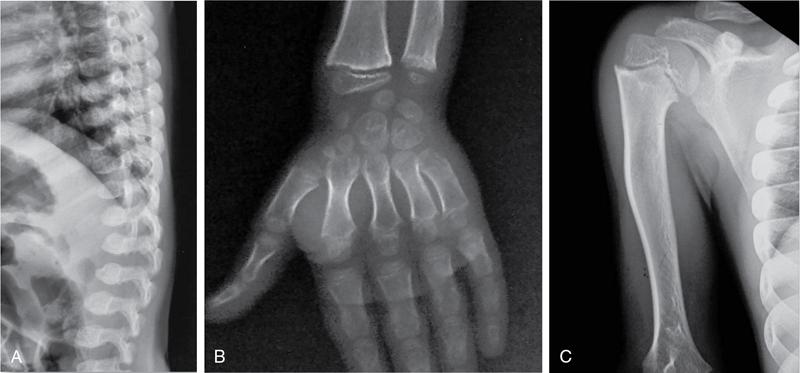

MISCELLANEOUS PAEDIATRIC RADIOGRAPHY – TECHNIQUES AND INTERPRETATION: SKELETAL SURVEY Padma V. Badhe The skeletal survey, generally performed in children, is a set of radiographs done in order to evaluate the entire skeleton. A skeletal survey, commonly used to evaluate skeletal dysplasias, acquired metabolic disorders and suspected child abuse, is still the key radiological investigation for the same. Hence, an explicit understanding of the technique along with the common disorders forms the basis of making a diagnosis in these paediatric pathologies. A skeletal survey is done for various skeletal dysplasias, non-accidental injury (battered baby syndrome) and suspected child abuse. It can also be done in cases of metabolic bone diseases, disseminated infections, multiple myeloma, eosinophilic granuloma. It is also used in evaluation of metastatic bone diseases and polyarticular arthropathy. Orthogonal views of the skull, spine, pelvis and one extremity are taken, preferable in standing position. For preterm babies/newborns, AP and lateral views of babygram may be taken. Projections: For skeletal dysplasias: Additional views: Both extremities may be taken if epiphyseal abnormalities and limb asymmetry is present. Focused views for specific pathologies may be taken. When a diagnosis remains uncertain, 1 year follow up is usually recommended. For preterm babies/newborns: AP and lateral views of babygram may be taken with additional specific views for extremities. For suspected non-accidental injury (NAI): AP and oblique view of chest is taken for better evaluation of the ribs. AP view of abdomen with pelvis. Both upper and lower limbs are evaluated. In lower limbs, two projections in AP and lateral (one with both femur including hip and knee joints; and another for foot and ankle) is taken. AP and lateral views of whole spine, skull. Oblique view of hands. A babygram should be avoided in cases of NAI, as subtle fractures are easily missed. Proper legal documentation while taking the views is very important and ideally two health care professionals must be present. For metabolic disorders: entire skeletal survey is usually not required. Specific views of hands, knees and spine may be taken with additional views depending on the suspected pathology. Centring point: Varies according to the part being examined. Angulation, collimation and orientation: Varies according to the part being examined. Images must be well collimated to obtain lower radiation dose. Detector size: Varies according to the part being examined: 8″ × 10″, 10″ × 12″, 11″ × 14″. Exposure: Ideally high kVp images are taken to reduce radiation dose. But in suspected NAI, low kVp/high mA images are recommended to better demonstrate findings. SID (Source Image Distance):100 cm Grid: Grids are not routinely used to image spine, pelvis, skull and abdomen in children. Radiation dosage: 0.3–3 mSv Essential image characteristics: Adequate spatial resolution, high signal to noise ratio, low kVp (50–70) for high contrast should be done. Excellent bone and soft tissue details are required. The presentation of skeletal dysplasia can range anywhere from minimal stunting of growth and bowing of limbs to severe dwarfism and multiple fractures. Knowledge of the commonly encountered dysplasias with an approach to arrive at a diagnosis is vital in any Radiologist’s practice The following flow chart summarizes the classification of important skeletal dysplasia: The following table summarizes the various dysplasias affecting the axial skeleton: TABLE 7.5.1.1 The following flow chart summarizes the working approach to skeletal dysplasias: Osteopetrosis (Albers-Schonberg disease/Marble bone disease) (Fig 7.5.1.1): Osteopetrosis clinically presents with anaemia/thrombocytopenia or cranial nerve compression. Radiological features include generalized increase in bone density with loss of medullary space. However, cortico-medullary appreciation with cortical thinning is also rarely seen. Bone within bone appearance with Erlenmeyer flask deformity is also noted. Pyknodysostosis (Figs. 7.5.1.2 and 7.5.1.3): patient presents with short stature. Unlike osteopetrosis, there is no anaemia. Radiographs show generalized increase in bone density with preserved medullary canal. There is mandibular hypoplasia with obtuse angle. Acro-osteolysis is also a feature. Dental caries with osteomyelitis of the jaw may be seen. Sclerosing dysplasia presenting as wavy undulating new bone formation. Usually monomelic, lower limb and along one side. The classic appearance is described as Dripping candle Wax sign. It is a Sclerosing dysplasia with radiological features of symmetric juxta-articular involvement in epimetaphyseal region. They are 1–10 mm in diameter and uniform in size. No metabolic activity is seen on bone scans. This skeletal dysplasia shows diffuse decrease in bone density with paper-thin cortex. Fractures heal in normal time but shows callus with poorly cellular matrix. Wormian bones and enlarged sinuses may be seen. Codfish vertebra (Biconcave vertebra) may be seen. Metaphyseal corner fractures are not seen in osteogenesis imperfecta that helps to differentiate it from battered baby syndrome. There are four types of OI out of which type one is most common (Figs. 7.5.1.6 and 7.5.1.7). The radiological features of MPS include Osteopenia and Universal platyspondyly. The intervertebral disc spaces are maintained. Proximal pointed metacarpals is an important radiological finding. Hurler’s syndrome show anteroinferior beaking with short and wide metacarpals. Varus deformity of humerus is characteristically seen in Hurler’s syndrome (Fig. 7.5.1.8). Mental retardation & corneal clouding is seen in Hurler’s syndrome whereas these Hunter’s disease has normal intelligence with no corneal clouding. Morquio’s syndrome shows central beaking (Fig 7.5.1.9). This skeletal dysplasia shows normal bone density with rhizomelic limb shortening and normal trunk. Narrowing of spinal canal is classically seen with decrease in the Interpedicular distance caudally. Other radiological features include trident hand (separation of middle & third fingers), Champagne glass pelvis (short, flat ilia and small sciatic notch), bullet nose vertebra and overexpansion of skull with narrow foramen magnum (Fig. 7.5.1.10). This skeletal dysplasia is characterized by normal bone density with dwarfism and normal craniofacial skeleton. The interpedicular distance is normal. There is severe platyspondyly with anterior tonguing (disappears at older age). Other radiological features include increased disc space, short stubby metacarpals, small irregular epiphysis and widened metaphysis. Anterior tonguing is a feature of Pseudoachondroplasia. This form of skeletal dysplasia involves the spine and epiphyses (Fig. 7.5.1.11). There is normal bone density with rhizomelia. Spine and Pelvis can be involved. Premature osteoarthritis can be seen. The other characteristic features include Platyspondyly and small irregular epiphysis. There are two forms Spondyloepiphyseal dysplasia Congenital and Spondyloepiphyseal dysplasia Tarda. Spondyloepiphyseal dysplasia Congenita is Autosomal dominant and shows pear-shaped vertebrae. Spondyloepiphyseal dysplasia Tarda is X Linked recessive with heaped up vertebrae. It has two forms. The first form is Conradi Hunermann syndrome which is autosomal dominant characterized by asymmetric limb shortening with metaphyseal flaring (Fig. 7.5.1.12). The Autosomal recessive form is Fatal in first few years. Rickets: Rickets refers to deficient mineralization of the growth plate in the paediatric population due to deficiency of vitamin D. In an immature skeleton, there is abnormal mineralization at the zone of provisional calcification in the metaphysis due to osteoid deposition resulting in widening of the growth plate. The features of rickets include fraying, splaying and cupping (Fig. 7.5.1.13). Fraying denotes indistinct margins of the metaphysis whereas splaying denotes widening of metaphyseal ends. Term ‘Cupping’ is used for increased concavity of the metaphysis. These findings are typically seen involving areas of active growth (e.g. distal femur and proximal tibia in the knee) Bowing is a result of associated osteomalacia leading to weakening of weight-bearing lower limb bones. Other bone deformities such as genu valga, genu varum, protrusio acetabuli can also be seen. The lower ribs may also be drawn inwards inferiorly by the attachment of the diaphragm this is called Harrison’s sulcus. Scurvy: Scurvy is a result of dietary deficiency of Vitamin C (ascorbic acid). The classic presentation is that of a patient with an increased bleeding tendency and osteopenia with poor wound healing. Features of scurvy include generalized osteopenia with cortical thinning termed as ‘pencil-point’ cortex. Other radiological findings include the periosteal reaction due to subperiosteal haemorrhage. Expansion of the costochondral junctions occurs forming scorbutic rosary. Bleeding into the joint spaces may result in hemarthrosis. Circular, opaque radiologic shadow surrounding epiphyseal centres of ossification may result from bleeding (Wimberger ring sign) (Fig. 7.5.1.14). Frankel line may be seen. It represents dense zone of provisional calcification. Lucent metaphyseal band is seen underlying Frankel line called as Trümmerfeld zone. Metaphyseal spurs may be seen that result in cupping of the metaphysis (Pelkin spur). Pelkin fracture (metaphyseal corner fracture) can also be seen. Images obtained must be of good resolution with adequate bone and soft tissue details. Additional views: They have already been described in positioning. CT Brain in can be done in cases of NAI to look for subdural hematomas. A skeletal survey is the first-line imaging modality for evaluation of skeletal dysplasia, nonaccidental injury and metabolic bone diseases. The skeletal survey must be tailored according to the respective indication. It helps to characterize syndromic patterns in skeletal dysplasias, with evaluation of complications. In cases of diagnostic dilemmas, additional focused view and occasionally yearly follow-up is recommended. A high index of suspicion is needed in utilizing skeletal survey as a diagnostic modality in NAI. At the same time, one must also remember the legal and social implications of making this diagnosis. BABYGRAM Babygram is a colloquial term used for a radiograph of the whole body of a newborn or just the chest and abdomen (thoracoabdominal babygram) on a single image. As the name suggests it is a rather non-targeted study. It is most commonly requested after line placement. Evaluation of skeletal abnormalities in a deceased foetus is typically performed using anteroposterior and lateral views of a babygram. It helps in pointing out skeletal causes of death in stillborn or dead foetuses. This will help the treating physician and parents understand the reason for baby’s death. This will also help in future genetic counselling of the couple. Sometimes chest or abdominal radiographs of the baby are requested but due to radiographers error or inexperience with small babies, there is inclusion of the region not to be assessed leading to a false babygram. Babygram is most frequently done after line placement in neonates, to view the position of the umbilical vein or artery catheter and to confirm appropriate placement. It is a useful modality in skeletal dysplasias (Fig. 7.5.1.15) like osteogenesis imperfecta, thanatophoric dysplasia and chondrodysplasia punctata. It can also be used for skeletal deformations probably caused by foetus akinesia and in cases of Caudal regression syndrome. In stillborn foetuses, it is used for evaluation of skeletal dysplasias prior to an autopsy (Fig. 7.5.1.16). It is also used in screening for surfactant deficiency and in cases of Necrotizing Enterocolitis in preterm babies where it can help to see the bowel dilatation, intramural and portal venous gas. It can be done in aneuploidies like trisomy 18 and in cases of sudden infantile death syndrome. All the essential equipment and room need to be prepared including the exposure factor. This should be done prior to placing the baby on the table to prevent any neonatal heat loss. Ensure that the baby is correctly identified. Give brief explanation to the patient’s parents regarding the procedure, its risks and benefits. Ensure that the accompanying relative is not pregnant (if female). Parents/guardians/nurses should be instructed to hold the baby with arms above the head and legs straight down. Sandbags/tapes can be used to immobilize the baby. Avoid taking the radiograph when baby is crying. Normal appearance: The endotracheal tube should lie in the lower third of trachea, distance can vary with position of baby’s head. Umbilical artery catheter has an inferior dip along the internal iliac artery, which then turns superiorly along the aorta. The tip should lie in the mid-thoracic aorta (T6–T10) or lower (L3–L4) away from aortic branches to prevent any thrombosis. Umbilical venous catheter does not have the inferior curvature, but rather a posterolateral angulation to the right near the liver through the ductus venosus. The tip should lie in the superior IVC or right atrium at T8/T9 vertebral level (Fig. 7.5.1.17). Portal venous gas may be seen initially after insertion. In a stillborn foetus, the approximate gestation age of the foetus and corresponding ossification centres must be known. In early gestation, the lack of appearance of an ossification centre may be mistaken for skeletal dysplasia. Both chest and abdomen should be included. In a rotated patient, the distance between the spinous process to medial end of clavicles will be asymmetric. The medial end of clavicle should overlap the lung apex, if above, suggests lordotic image. Motion artefacts to be reduced as much as possible. A crying neonate may result in an expiratory film, and hence must be evaluated accordingly. In evaluation of skeletal dysplasias in the newborn, additional views of skull and hand have to be obtained. Baby gram is a useful diagnostic investigation for position of the paediatric umbilical catheters. It helps in general survey in skeletal dysplasia (Fig. 7.5.1.18). It is a simple, effective study in deceased foetus for diagnosis and further counselling, sometimes obviating the need for an autopsy. As baby gram is a non-targeted study, it increases the dose of radiation for the baby. As the exposure settings remain same for the entire body of the baby, the quality of the image decreases. This increases the chances of missing subtle findings. The babygram in a neonate is currently used to localize umbilical catheters. In stillborn fetuses, it is still an important study for documenting and confirming skeletal dysplasias. Understanding the normal appearance as per gestation age and patterns of various common skeletal dysplasias is essential for evaluation. Being a non-targeted study, it should not be used as an alternative study to evaluate the chest or abdomen considering radiation exposure and poorer image quality. INVERTOGRAM Invertogram was first described by Wangensteen and Rice in 1930. It was used as a first investigation to be ordered in evaluation of infants with clinically diagnosed or suspected Anorectal Malformation (ARM). ARM is a serious but surgically treatable congenital malformation with approximate incidence of 1 in 5000 live births. Though the diagnosis of this condition is based on clinical history and physical examination, imaging plays an important role in deciding the type of ARM, and associated complications to aid in management. International classification of anorectal malformations is as follows. Syndromic association is seen as a part of VACTERL defects, trisomy 21 13 and 18, Klippel Feil syndrome, cat eye syndrome etc. The main indication of Invertogram is to evaluate anorectal malformation in a neonate. A radio-opaque marker is placed over the external anal opening. Infant is held inverted by holding both thighs, maintaining this posture for at least 5 minutes before taking an X-ray in true lateral position (Fig. 7.5.1.19). Exposure is made during inspiration. The Invertogram should ideally be done 24 hours after birth as, the rectal gas may not reach the terminal segment if study is done too early. Pubo-coccygeal line (PCL) is drawn from upper border of pubic symphysis (which corresponds to centre of pubic bone on lateral X-ray) to sacrococcygeal junction. I point is the inferior most point of ischial ossification centre. A line which is drawn parallel to PC line passing through the I point is called I line. ‘A’ point is represented by marker placed at anal pit. The position of rectal pouch gas shadow is observed with respect to these lines and appropriate diagnosis is made (Fig. 7.5.1.21). A diagnosis of high ARM is made when gas shadow of rectal pouch is cranial to PCL. If rectal pouch gas shadow is in between PCL and I line, it is called as intermediate ARM and if it is caudal to I line, it is diagnosed as low ARM. Gas in urinary bladder or vagina or beaking of gas shadow of rectal pouch indicates fistula into one of these sites. Associated congenital abnormalities like spinal defects are also looked for in the invertogram (Fig. 7.5.1.22). Invertogram done too early (less than 24 hours) may not demonstrate rectal gas. Meconium plugging the terminal segment gives false position of the rectal gas. Positioning can cause discomfort to child and an irritated crying child actively contracts the sphincter muscles, pushing the gas shadow higher. Rectum may be pulled cephalad due to gravity in inverted position. The rectal gas may escape through an associated fistula. Erroneous interpretation can also occur due to sacral anomalies and when gas in vaginal cavity is misinterpreted as distal rectal gas. Both ischial bones should superimpose and terminal blind loop should be well distended. It is an easily available modality and can be done quickly, does not require additional equipment. It has lesser radiation dose as compared to CT invertogram. It provides a rough guide as to the type of ARM and decides management. Higher localization of obstruction due to various causes like meconium plugging, imaging done too early etc. as described above in pitfalls. It is more uncomfortable to the baby as compared to the prone cross-table lateral view, and a crying baby contracts the puborectalis leading to erroneous results. K. L. Narasimharao et al. modified the technique and proposed cross-table lateral view for evaluation of infants with ARM’s which has shown equal or better information and has now replaced invertogram (Fig. 7.5.1.23). Prone cross-table lateral view is considered equivalent or even better in determining the level of anomaly. Positioning is in this view is prone in genupectoral position (at least for 3 minutes). It is taken in true lateral and during inspiration. The lines used to delineate types of ARM is essentially the same as in an invertogram. It is preferred over invertogram as relatively easy positioning of the infant and less discomfort allows for better cooperation of neonate during the study. It also eliminates the effect of gravity. ARM with fistula is better delineated as, in an invertogram, fistula/gas is at the highest level and gas may escape through it. CT invertogram is another modality that delineates anatomy better but is rarely used. In the era of cross-section imaging, MRI and USG have opened new modalities for accurate diagnosis of ARM, but invertogram being readily available, inexpensive, quick and cost-effective is used as first investigation for evaluating a patient with suspected or confirmed case of ARM. Cross-table lateral view has replaced invertograms as it is more patient-friendly and equally effective. UPPER GASTROINTESTINAL SERIES Rushit S. Shah An upper gastrointestinal (GI) study is a radiographic examination of the GI tract from the pharynx to the ligament of Treitz after oral administration of contrast agent. The use of upper GI studies is gradually declining with the increasing availability of paediatric endoscopy and the challenge for the modern radiologist to work in conjunction with the surgeon and gastroenterologist to select the right patients for an upper GI series. However, the upper GI series remains the key for demonstrating many anatomical abnormalities. The upper GI series is also useful in evaluating gastro-oesophageal reflux in conjunction with 24 pH monitoring. The upper GI examination is useful in evaluating many conditions including but not limited to: